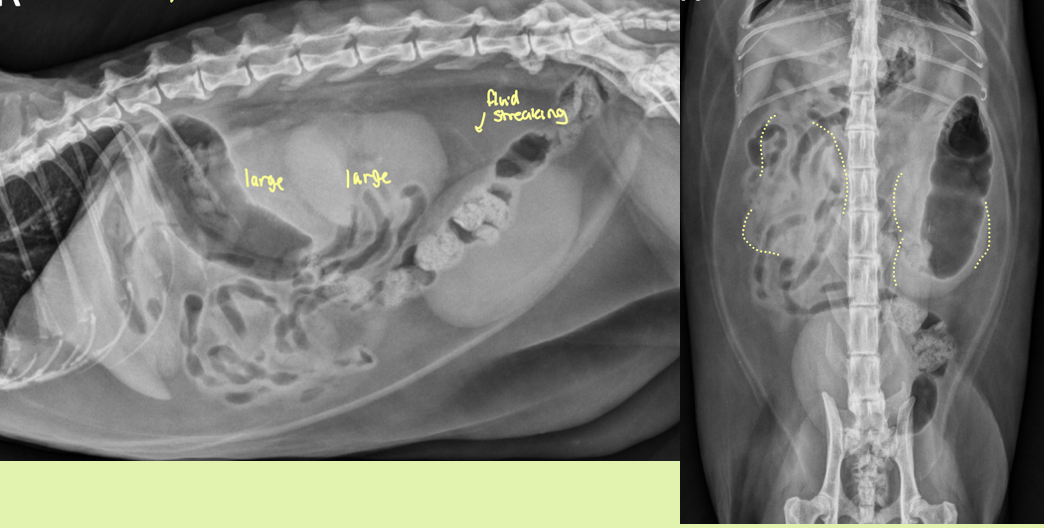

enlarged smooth kidneys with distended pelvis ± distended ureters

hydronephrosis

hydronephrosis is caused by

partial or complete obstruction of urine outflow in renal collecting system or ureters

4 causes of congenital vs acquired hydronephrosis

Congenital

kinking or partial obstruction of ureters 2° to kidney or ureteral malposition

Stenosis

compression from ureterocele

associated with ectopic ureters or other congenital malformations without true obstruction

Acquired

Obstruction from urinary calculi, neoplastic or inflam masses

accidental ligation

ureteral stricture

parasites (dioctophyma renale)